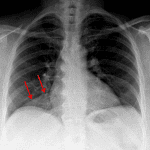

Age: 51

Sex: Female

Indication: Cough

Findings

- No focal airspace opacification

- No pleural effusion or pneumothorax

- Normal size and configuration of the cardiopericardial silhouette

- Clearly marginated hazy density along the anteromedial right lung base

Diagnosis

- Prominent pericardial fat

No evidence of acute cardiopulmonary disease.

Clearly marginated hazy density along the anteromedial right lung base likely represents prominent pericardial fat.